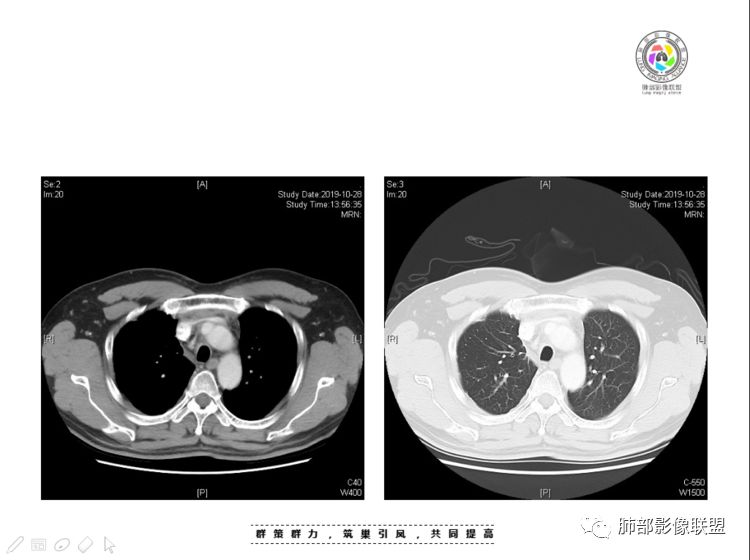

穿越七海的风:右前纵隔占位,恶性肿瘤,生殖来源?右肺实变是占位or肺不张?考虑为部分肺不张FeNo:右前纵隔占位,右肺结节,胸膜凹陷,小尾巴,右肺不张,考虑恶性杨旭华:恶性,前纵隔肿物,与血管关系密切,上腔静脉变窄,右肺野一元论考虑叶间裂增厚,恶性胸膜间皮瘤可能大小丽:到底是纵隔来源还是胸膜来源?我怎么倾向于胸膜来源,和叶间胸膜关系密切,而且纵隔内上腔静脉是向内侧推移。胸膜肿瘤(间皮瘤?SFT?)包裹性胸腔积液?马春平(张家港市一院胸外科):前纵隔占位,左无名受压,右大量胸腔积液可能是胸导管汇入处侵犯受压,考虑纵隔鳞癌孙冰伟:右上纵隔占位,也感觉和叶间胸膜关系密切,右侧胸膜局限性增厚,考虑恶性可能性大灵:前纵隔占位,血性胸水,胸膜凹凸不平,查见肿瘤细胞,结合免疫组化考虑胸腺癌。鉴别胸膜间皮瘤。采莲:右前上纵膈旁可见类圆形肿块,纵隔血管内移,感觉来源于胸膜,肿块内密度低,似水样密度,右侧胸膜广泛增厚,少量胸腔积液。心包少量积液。考虑胸膜间皮瘤,鉴别肺癌并胸膜转移?水晶石头:患者中年男性,胸闷15天。有“高血压、慢性肾小球肾炎”病史。查肿瘤标志物正常,胸水提示渗出液,胸水病理查见瘤细胞。胸部CT:右肺上叶后段结节、斑片影,见胸膜牵拉、包裹积液及部分纤维条索灶,似见卫星灶,右侧胸膜增厚。前纵隔脂肪密度增厚,右侧可见类圆形低密度(液体)肿块,边缘光滑。综合考虑右肺腺癌并胸膜转移,结核可能。周太狼:考虑纵隔胸膜来源肿瘤,恶性,胸膜间皮瘤伴转移?徐飞:中年男性,影像为右侧胸腔及叶间积液,叶间胸膜增厚轻度强化。前纵隔右侧心缘旁团块,可见坏死。胸水见癌细胞,综合考虑恶性,胸腺癌伴转移。小赵:中年男性,血性胸水,常规查见癌细胞,李凡他实验阳性。胸部CT示前纵隔见不均匀密度影,与邻近大血管分界不清,囊变坏死明显,增强扫描呈不均匀强化,心包及右侧胸膜增厚,并心包及右侧胸腔少量积液。综合考虑胸腺癌。右肺中叶病变周围见多发纤维条索,支气管部分进入病灶,考虑炎性病变。流心明智:患者,男性,50岁。胸闷15天。高血压20年,慢性肾小球肾炎15年。肿标正常,胸水提示渗出液,胸水查见癌细胞。胸部CT:右肺肿块影,斑片影,索条影,可见胸膜牵拉、多发包裹积液,纵隔上腔静脉受累,心包受累。综合考虑:ROSE似腺?考虑右肺腺癌并胸膜转移,心包受累。鉴别胸腺Ca、淋巴瘤,纵隔病变不懂,等老师们精彩分析。王秀仙:前纵膈囊实性肿块,与纵膈分界不清,心脏大血管及上腔静脉受压向内后移,右侧后胸膜、侧胸膜增厚,右侧叶间裂不规则增厚,心包积液,根据腔静脉移位情况,考虑纵膈胸膜来源恶性肿瘤,胸膜间皮瘤?鉴别胸腺癌并胸膜转移。高广飞:上纵隔占位,右侧叶间胸腔积液,需考虑恶性自信人生:多发囊实性病灶,包裹性积液,考虑胸膜来源 只是没有看到壁结节,恶性胸膜间皮瘤巴伟:前上纵隔占位,胸膜及心包结节,考虑胸腺瘤或癌,右肺病灶,先考虑陈旧炎性病变。Lenle董:前纵隔占位,部分边缘模糊,病灶内囊变?坏死?上腔静脉受侵,考虑胸腺癌;叶间片状影,强化明显,炎性考虑。常志强:前纵隔囊实混杂密度肿块,边界不清,实性部分强化明显,结合胸水内见癌细胞,考虑恶性肿瘤伴转移。飞鹰行动:前纵隔占位,软组织密度及囊性密度,实性部分密度均匀,致密,病灶与周围血管分界不清,增强后病灶强化有类似不温不火强化,部分血管受侵犯,右肺见肿块样病变及条索状病变,一元论,考虑淋巴瘤,二元论,考虑胸腺瘤B2—B3伴右肺病变。尽量一元论考虑,淋巴瘤可能。看图说话:右肺索条病灶,边缘膨隆,胸膜牵拉,考虑右肺癌伴胸膜转移。晨:前纵隔囊实性肿块,与纵隔分界不清,右侧后胸膜、侧胸膜增厚,右侧叶间裂不规则增厚,考虑纵隔胸膜来源恶性肿瘤,考虑胸腺癌并胸膜转移。丽:中年男性,前纵隔囊实性肿块,呈偏心性生长,临近大血管受压推移,增强后实性部分不均匀强化,心包可见条形积液,考虑胸膜来源恶性肿瘤,胸腺癌可能大。另右肺多发斑片状高密度影及实变密度影,实变影呈均匀强化,右侧胸膜局限性增厚,考虑炎性病变。小飞:右前纵隔囊实性占位,实性部分明显强化,右侧叶间胸膜增厚,右侧胸腔积液,心包积液,考虑恶性胸腺瘤!尘缘:支持恶性胸腺瘤(囊实性肿块,实性强化,且侵犯纵隔,脂肪间隙模糊)伴肺内及胸膜转移。浪迹天涯:考虑侵袭性胸腺瘤——胸腺前纵隔占位,周围脂肪间隙模糊不清。尘缘:不除外另一种可能:二元,肺内腺癌合并胸膜转移,纵隔的畸胎瘤可能。一米阳光:晨读中年男性,右肺结节影,叶间裂及胸膜增厚牵拉,右侧胸水。心包多发结节改变。胸水查见癌细胞。考虑,腺癌并转移。鉴别,胸膜间皮瘤并转移前纵隔囊实性占位,二元考虑。心灵鸡汤:老年男性,右肺中叶外段长条状软组织密度影,边缘膨隆,邻近胸膜牵拉,部分胸膜有栽脏,右中叶外侧段支气管堵塞,常规考虑恶性肿瘤,腺癌可能,结核、鳞癌不除外,另右肺上叶斑片影,小叶性肺不张?右前纵隔囊实性不规则形密度影,其内见部分脂肪样极低密度影,与邻近血管边界不清,心包外膜有侵犯,增强未见纵隔窗平扫,实性及分隔见增化,其内低密度影未强化,考虑低度恶性纵隔肿瘤,间皮瘤可能,畸胎瘤、淋巴瘤待排,建议支气管镜及穿刺活检。曹志勇:右前纵隔考虑来源于胸膜的恶性肿瘤,右肺内病灶考虑鳞癌,二元德芙~云味:中年男性,右肺见结节、斑片影,右侧包裹积液、胸膜牵拉,纤维条索,前纵隔囊性占位,考虑腺癌、并转移。欧阳英:右前中纵隔囊实性肿块及右肺内结节灶,支持恶性肿瘤,胸腺癌并肺内转移可能张延军:前纵隔见不规则软组织影,密度不均,右侧缘见囊变区,纵膈及侧胸壁胸膜增厚,增强呈不均匀强化,右肺中叶见结节灶,近段支气管阻塞,叶间胸膜不规则增厚,考虑1:右肺中叶腺癌伴纵膈及胸膜转移;2:前纵膈侵袭性胸腺瘤并胸膜侵犯,中叶炎性改变?彭君:老年,前纵隔占位 ,坏死边缘清, 侵犯心包 右侧胸膜及叶间胸膜结节 ,少量胸水, cea不高 ,考虑恶性, 间皮瘤可能 ,转移待除外。毛勤香:恶性没问题,胸水查见癌细胞,一元还是2元,右肺中叶肿块,边缘毛糙,局部似有毛刺,周围有粘连,右侧胸膜腔少量积液,胸膜增厚多发结节,含叶间裂结节,纵膈脂肪间隙模糊,纵膈胸膜增厚,心包增厚积液,右前那个类圆形低密度肿块,纵膈血管内移,我考虑胸膜来源可能性大,综合考虑,一元肺腺癌并多发转移,二元考虑胸膜间皮瘤并多发转移,肺内炎症不张。

本例纵隔与肺内两处病变,回顾总结分析:

1、右肺内病灶,病灶呈结节样,边缘欠规则,局部膨隆,叶间裂胸膜牵拉凹陷,再看相应支气管腔堵塞截断,临床资料胸水中查到癌细胞,均提示病灶倾向恶性,腺癌的病理意见与之相吻合。

2、前纵隔内病灶囊实性混杂密度病灶,囊性病灶主要位于右侧,张力较高,有分隔影,囊壁右侧缘光整,病灶左侧实性部分边界不清明显强化,病灶肺瘤交界面大部分边界清楚,部分模糊。

前纵隔肿块伴囊变坏死常见以有胸腺瘤、胸腺癌、淋巴瘤和生殖细胞肿瘤。